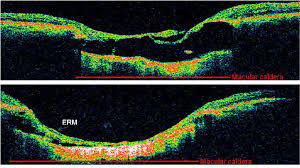

Ear diseases: Age-related degeneration, edema (diabetic or postoperative), macular hole, epiretinal membrane.

The bottom photo shows us the surface of the retina (like taking a picture of your skin). OCT shows us what's happening down from the surface (like seeing the layers of skin in an incision). Many conditions, such as macular edema, can only be seen clearly on OCT.